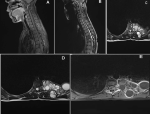

Diagnostic assessment: spinal magnetic resonance imaging showed a multilobulated lesion with solid and multivesicular components, centered on the left costovertebral groove at the D6-D7 level. The lesions were hypointense on T1-weighted images and hyperintense on T2-weighted images, with peripheral contrast enhancement. The involvement extended to the D6 and D7 vertebral bodies, posterior vertebral arches, adjacent paravertebral muscles, and resulted in extradural spinal cord compression. A displacement of the left hemithorax was observed, without any associated pulmonary parenchymal lesion (Figure 1). The clinical presentation in a young woman living in a rural area, together with the imaging findings, strongly suggested the diagnosis of costovertebral hydatidosis. The extension workup, including chest radiography and abdominal ultrasound, revealed no additional hydatid localizations, allowing the diagnosis of isolated primary costovertebral hydatidosis. Hydatid serology was not performed. Laboratory investigations showed normal inflammatory markers and no eosinophilia.

Figure 1: spinal magnetic resonance imaging: A) sagittal T1-weighted image, the lesions appear hypointense on T1-weighted images; B) sagittal T2-weighted image, hyperintense on T2-weighted images; C, D) axial T2-weighted images, hyperintense on T2-weighted images; E) post-contrast T1-weighted axial image: multilobulated lesion with both solid and multivesicular components, centered on the left costo-vertebral groove at the D6-D7 level, with peripheral contrast enhancement.

Figure 1:spinal magnetic resonance imaging: A) sagittal T1-weighted image, the lesions appear hypointense on T1-weighted images; B) sagittal T2-weighted image, hyperintense on T2-weighted images; C, D) axial T2-weighted images, hyperintense on T2-weighted images; E) post-contrast T1-weighted axial image: multilobulated lesion with both solid and multivesicular components, centered on the left costo-vertebral groove at the D6-D7 level, with peripheral contrast enhancement